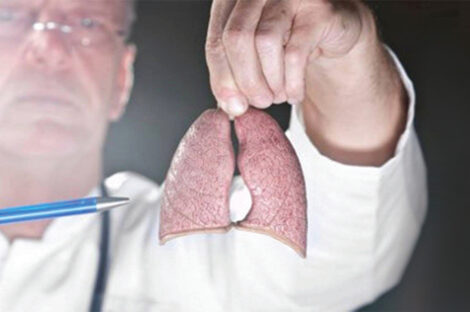

يمكن تخفيف العديد من المشاكل الصحية التي تهدد طول العمر من خلال الالتزام بنمط حياة صحي. ويعد السرطان أحد الأسباب…

يشكل سرطان الرئة المسبب الأول للوفيات التي تحصل نتيجة لمرض السرطان، سواء بين النساء أو بين الرجال. اكتشف علماء من…